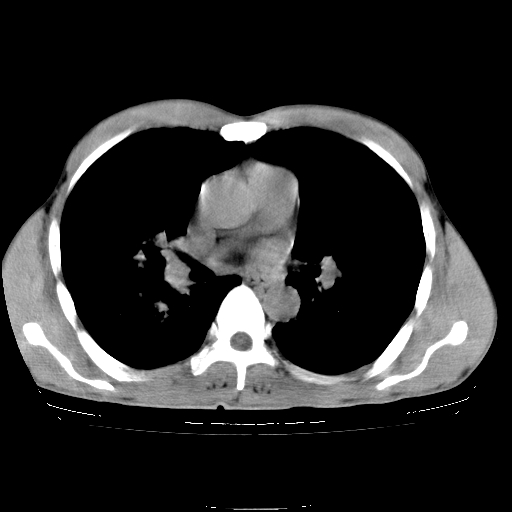

以下是引用yangyudong333在2008-4-29 5:38:00的发言:[br]比较典型的矽肺结节.支持[br]诊断依据:[br] 1.x线表现:[br] ①典型矽肺为多发直径 1~3mm 小结节,即矽结节,由胶原纤维和硅尘构成,可融合成团块,好发于上肺。[br] ②团块周围常有肺大泡。[br] ③胸内淋巴结增大、钙化。如肺门淋巴结呈蛋壳样钙化有助于与其他尘肺区别。[br] ④胸膜常广泛粘连、增厚。[br] 2.ct表现[br] ①两肺散在大小较为一致的小结节影,其密度较高,边界清楚。[br] ②小结节可融合为较大团块影,直径约 1cm ,甚至可达 10cm以上,易发生在上叶。[br] ③小结节周围常并有小叶中心气肿或弥漫性肺气肿。

以下是引用liuyue在2008-4-28 22:30:00的发言:[br]比较典型的矽肺结节.[br]请结合临床及化验除外矽肺合并肺结核之可能.